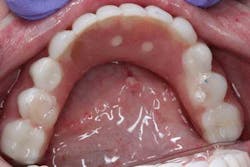

Surgery commenced. Implants on the lower arch were placed first (figures 7 and 8) and then we switched to the maxillary. The teeth were removed (figures 9 and 10) and the ridge was evened out (figures 11-13). The implants were aligned with the denture (figure 14) and then placed accordingly (figures 15-17). Healing caps were put on, and we were ready to start the restorative phase (figures 18-19).

The maxillary arch was indexed first as there was support from the palate to reference position (anterior/posterior) (figure 20). Then the lower was put into position to gain proper vertical dimension and occlusion. It, too, was then indexed; both upper and lower were given to the lab technician to start the conversion process. Next, impression copings were placed (one arch at a time) and secured with paperclips; a full-arch PVS impression was taken and likewise sent to the lab (figures 21-23). Finally, after the conversion process was completed, the bridges were secured in place on the multiunit abutments, torqued to 15nCm, and covered. Bite was adjusted and follow-up care was arranged (figures 24-26).